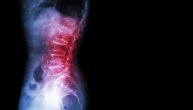

Degenerativne promene, poput spondiloze ili degeneracije intervertebralnih diskova, čest su razlog hroničnog bola u leđima. Usled ovih promena dolazi do bola, ukočenosti i osećaja hladnoće. Problemi su izraženiji tokom jutra i posle mirovanja. Terapija uključuje redovne šetnje, korekciju držanja tela, fizikalnu terapiju i lekove protiv bolova koji se mogu kupiti bez recepta.

Hernija diska je protruzija (“curenje”) diska koji se nalazi između pršljenova kičmenog stuba. Najčešće se javlja u vratnom i lumbosakralnom delu kičme, a posledica je povrede ili starenja i degenerativnih promena. Kada dođe do “izbočenja” ili pucanja diska, dolazi do pritiska na nerve i bola koji se širi u ruke ili noge; moguć je osećaj hladnoće i utrnulosti. Pojedini pacijenti imaju skoro neprimetne simptome, ali bol može biti intenzivan i pogoršavati se pri savijanju, dizanju tereta ili posle dužeg sedenja. Savetuju se mirovanje, fizikalna terapija prema uputstvu lekara i analgetici za kontrolu bola.